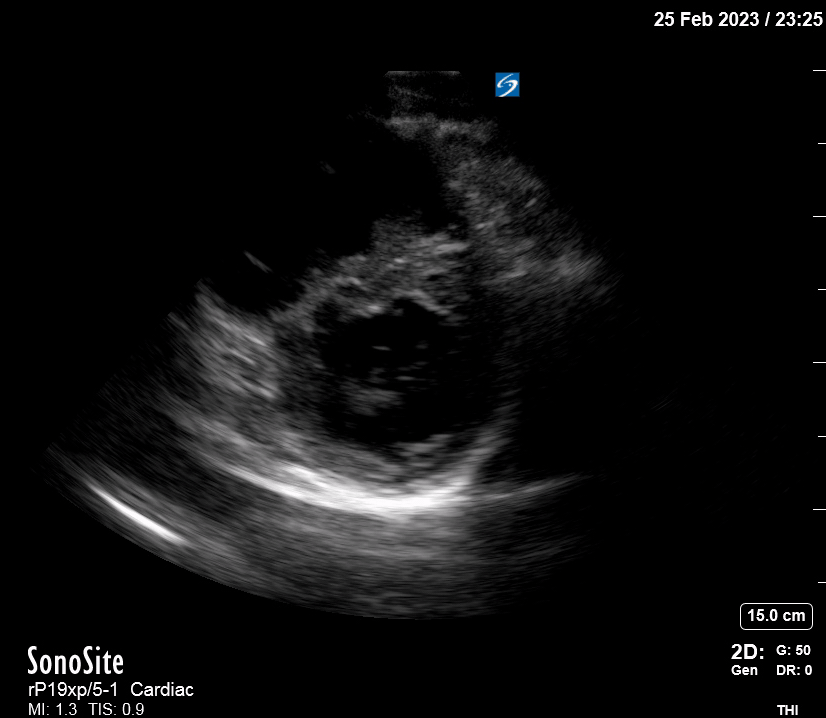

Equality: is the RV dilated or significantly impaired?

Normally, the RV is a low-pressure, thin-walled, high-compliance chamber that wraps anteriorly around the muscular, cone-shaped LV. The normal RV : LV diameter ratio is 0.6 : 1.

When the pulmonary artery pressure rises, the RV will dilate, altering the normal RV:LV ratio. Although sacrificing sensitivity, the use of equality (1:1 ratio) as a cutoff can achieve a specific estimation of RV strain. If imaged correctly by a trained operator, the presence of an RV:LV ratio > 1 is highly specific for RV strain.

RV dilation can be acute, chronic, or acute-on-chronic. However, in patients presenting with undifferentiated chest pain, shortness of breath, hypotension or syncope, the presence of any RV dilation should raise suspicion for acute pulmonary embolism (PE). Furthermore, in a patient in shock, the presence of RV strain may signal the need for aggressive therapy – emergency thrombolysis.

THE VIEWS

The A4C view provides an accurate chamber size comparison. However, achieving a proper A4C view (avoiding foreshortening or ballooning, and visualising the four chambers with a vertically oriented interventricular septum) can be a challenging exercise of image acquisition. Additionally, the PSAX view at the level of the papillary muscles shows both LV and RV side by side and is useful to assess function and size. When RV pressure is high, the septum will be pushed and flattened towards the LV, resulting in the characteristic “D-shaped” LV or “D sign”.

PITFALLS

When comparing size, beware of correct image acquisition, as oblique planes lead to misinterpreting the RV:LV ratio. For apical views be sure to slide the probe sufficiently laterally on the chest wall so that it lies over the true apex. Also, be sure to obtain a real horizontal plane, avoiding foreshortening (ballooning). For the PLAX view it is useful to fan through the heart’s long axis, making sure that LV visualization is maximized relative to the RV. Furthermore, an understanding of probe placement and marker orientation conventions is fundamental. If inadvertently scanning in reverse orientation, the normally larger LV could be mistaken for an abnormally enlarged RV.